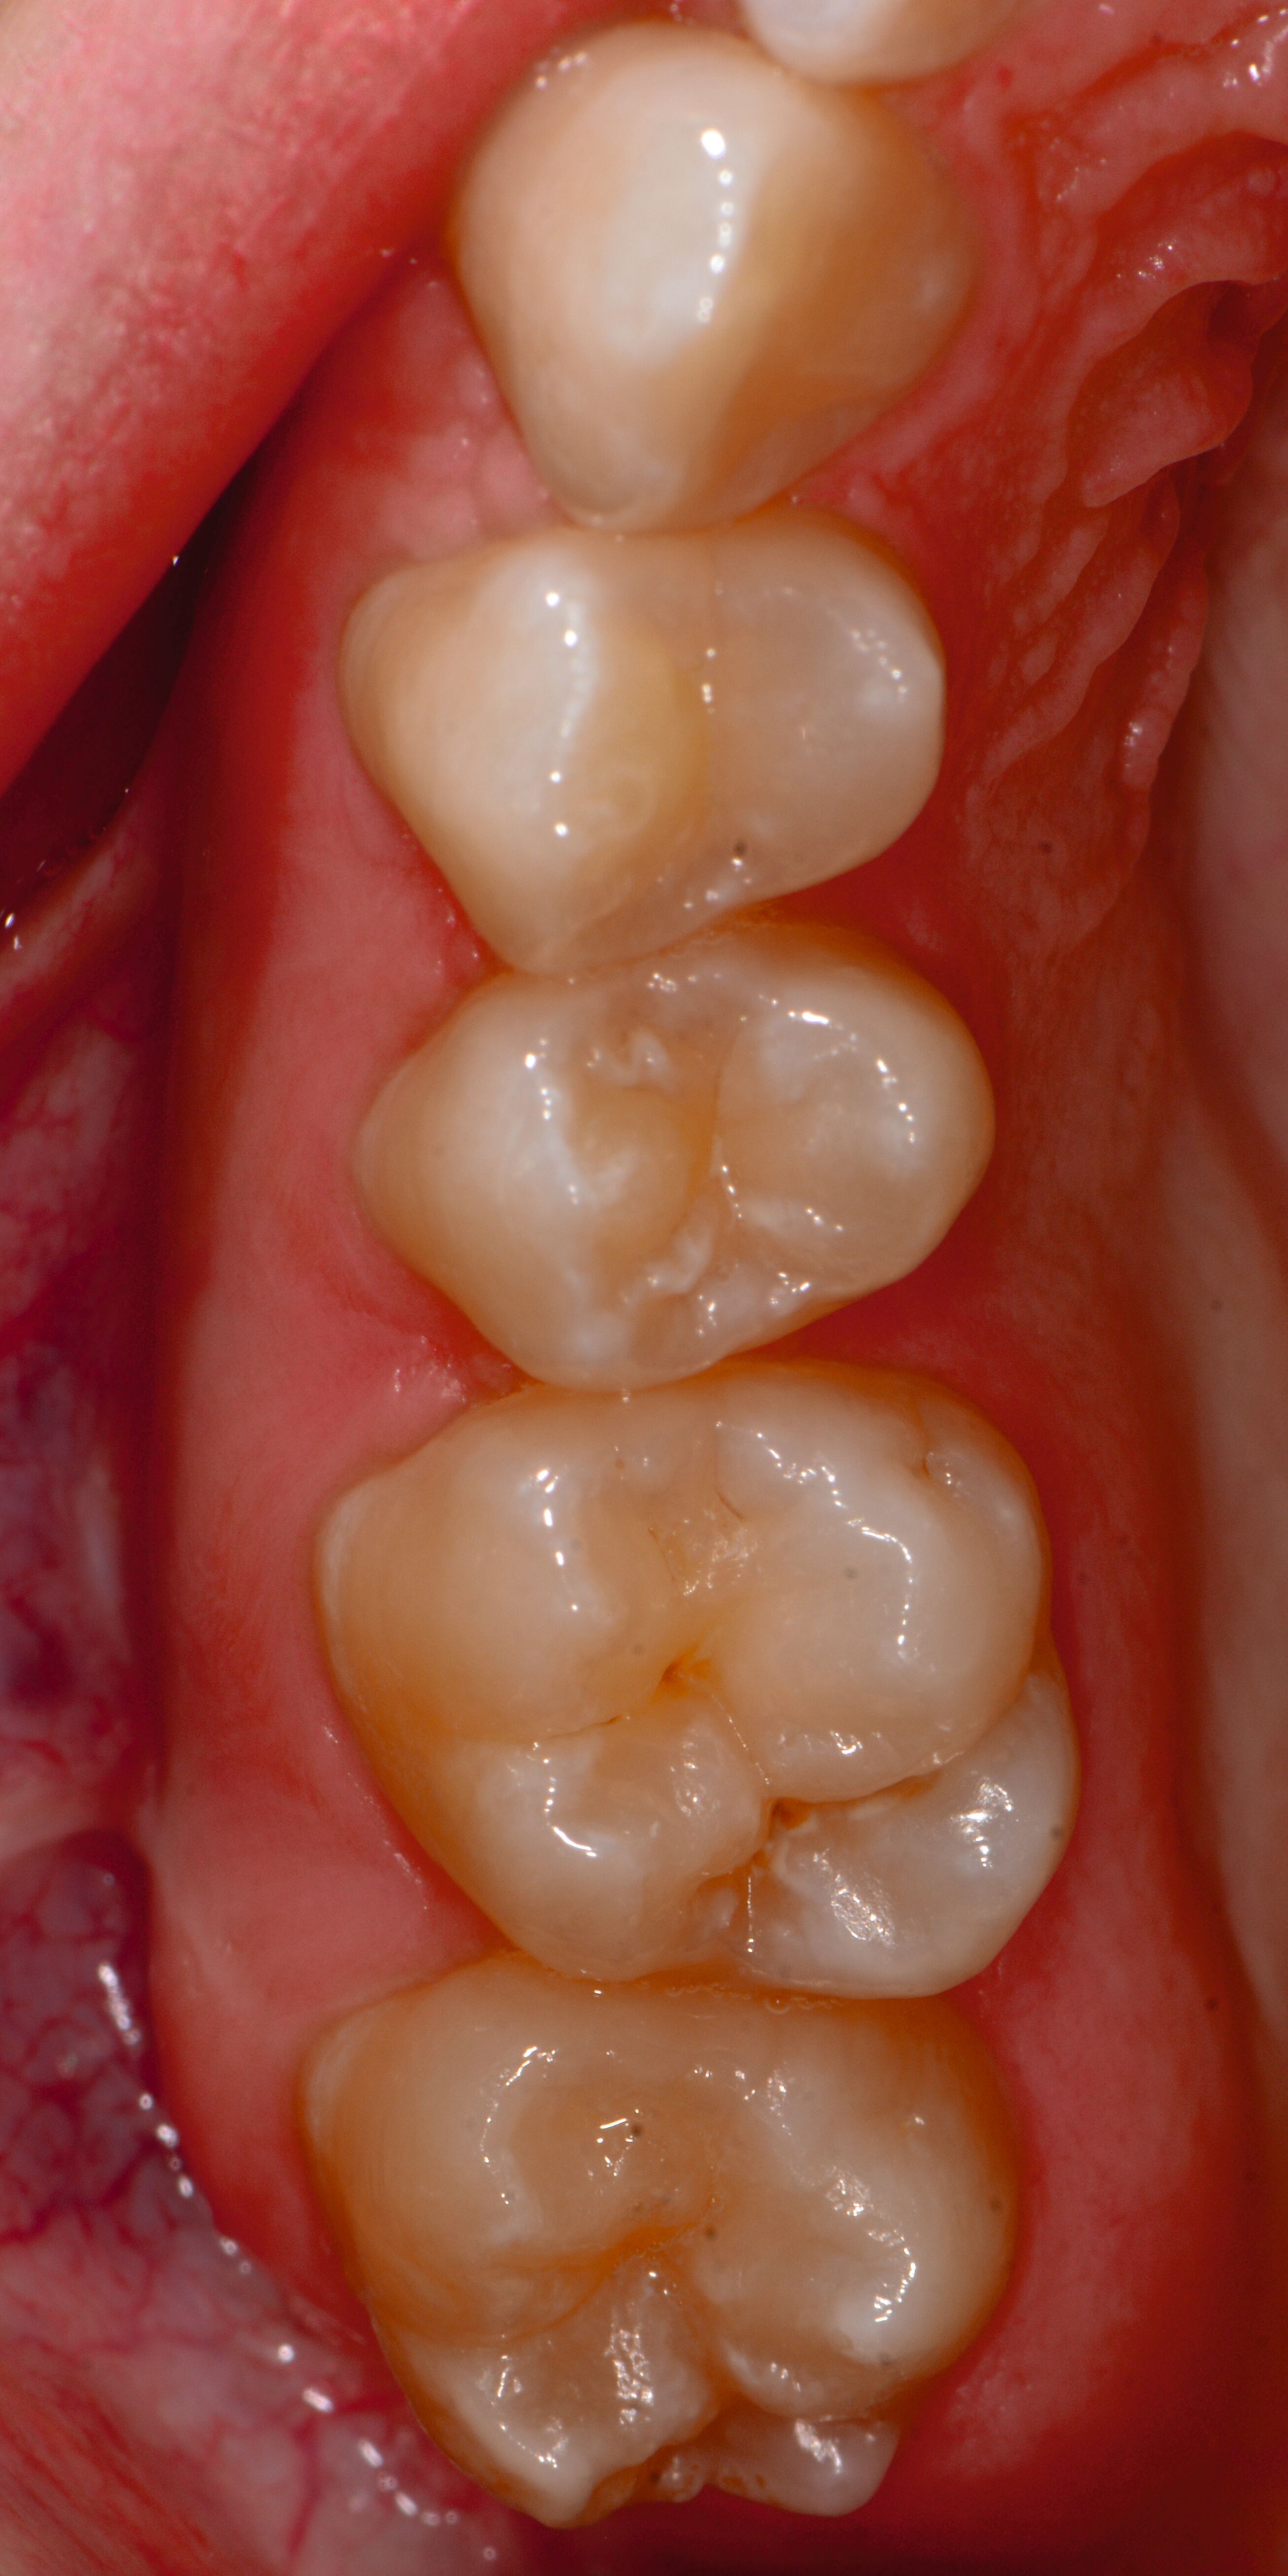

Das klinische Erscheinungsbild an bleibenden Zähnen zeigt typischerweise weißlich-gelbe bis gelblich-braune Opazitäten, die zumindest in einigen Bereichen durch eine scharfe Abgrenzung (engl.:„demarcated opacities“) zum gesunden Zahnschmelz charakterisiert sind (Abbildungen 3 und 4). Die abgegrenzten Hypomineralisationen befinden sich mehrheitlich im Bereich der inzisalen Kronenhälfte unabhängig von dem Auftreten an Front- oder Seitenzähnen. Die Ausprägung am Zahn kann dabei auf einzelne Areale oder Höcker begrenzt sein.

Bei einer schwerwiegenderen Ausprägung sind Zahnflächen vollständig betroffen, mitunter alle Zahnflächen an einem Zahn. Die Verteilung in der Dentition beziehungsweise an den Indexzähnen ist gleichermaßen variabel und betrifft nicht nur die Defektgröße, sondern auch die Farbe und Festigkeit. Was die Festigkeit betrifft, gilt als die Faustregel: Je dunkler die Farbe des Schmelzes, umso weicher beziehungsweise poröser und damit minderwertiger wird dessen Qualität sein. Damit reduziert sich seine kaufunktionelle Belastungsfähigkeit, was insbesondere an ersten bleibenden Molaren von klinischer Relevanz ist.

Für die Dokumentation und Klassifikation der MIH wurden verschiedene Systeme vorgeschlagen. Als historisch und veraltet gilt der (modifizierte) DDE-Index. Demgegenüber haben die Kriterien der EAPD – abgegrenzte Opazitäten (Abbildung 3 und 4), Schmelzeinbrüche (Abbildung 5), atypische Restaurationen (Abbildung 6) – mittlerweile die weiteste Verbreitung gefunden. Diese wurden 2003 erstmals zur Beschreibung der MIH auf empirischer Basis publiziert [Weerheijm et al., 2003] und den Jahren 2010 und 2022 im Rahmen der damaligen MIH-Workshops bestätigt [Lygidakis et al., 2010; 2022].